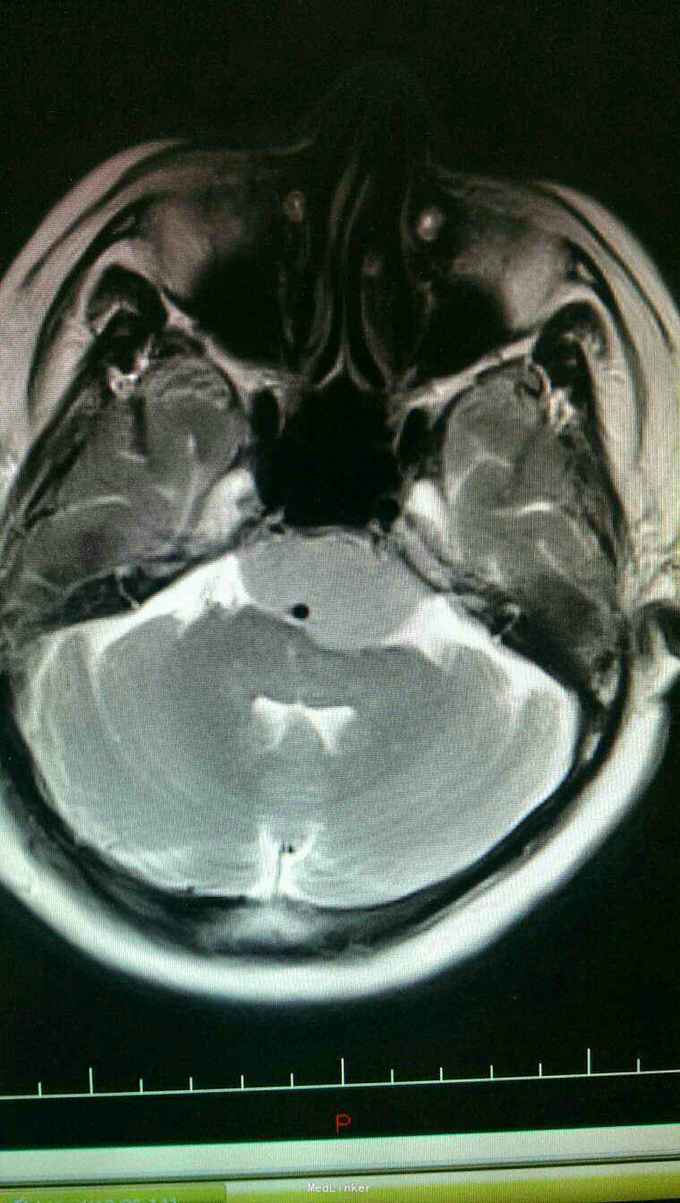

入院诊断:岩斜区脑膜瘤。完善术前准备,于全麻下行右侧颞下入路,岩斜区肿瘤切除,术中保留拉贝静脉,剪开小脑幕,近全切除肿瘤。

患者术后病情稳定,岩斜区位于颞骨岩部背面与枕骨斜坡部的岩斜裂汇合处,从岩骨尖至颈静脉孔。内侧至斜坡中线,外侧至第Ⅴ、Ⅶ和Ⅷ脑神经,上缘为鞍背,下缘为颈静脉孔水平;下方为枕骨大孔区。岩斜区脑膜瘤由于位置深,毗邻重要解剖结构,很难实现肿瘤全切除,且有较高的术后致残率,一直是神经外科手术的治疗难点。颅内脑膜瘤约0.3%~1.0%起源于岩斜区,是岩斜区最常见病变。它向上可侵犯岩骨尖、小脑幕、Meckel腔、鞍旁和海绵窦;向下侵犯内听道和颈静脉孔;向内侧达脑干和椎-基底动脉。当肿瘤很大时,可包绕同侧Ⅲ~Ⅺ脑神经。患者临床可表现头痛、复杂的脑神经麻痹、共济失调等症状,严重者表现为偏瘫、认知功能障碍。岩斜区脑膜瘤多数表现良性过程,目前,仍以手术切除为首选治疗方式。 岩斜区脑膜瘤手术技术非常关键,需要熟悉岩斜区解剖关系并有丰富的显微操作经验。在术前放置腰穿引流,或术中甘露醇应用可明显降低脑组织压力,减少牵拉造成的副损伤。提前对脑膜瘤基底的处理可有效避免肿瘤持续出血造成的蛛网膜界面消失。肿瘤的生长将神经、血管拉伸或包绕,尤其是复发的肿瘤,会破坏蛛网膜界面,侵犯脑干软脑膜。手术时应仔细分辨和保护。肿瘤囊壁与神经、血管外膜和脑干粘连,不应勉强分离,以保护下方结构。 待术后平稳复查头Ct。